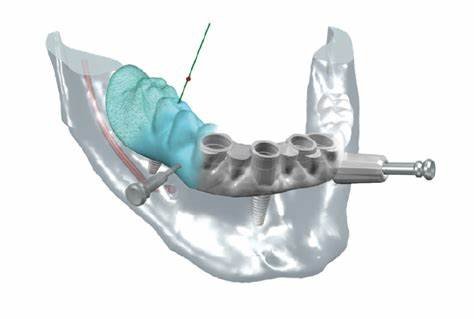

- Mandibular nerve mapping:

- Clear visualization of the inferior alveolar nerve canal

- Maintenance of a minimum 2mm safety distance from the nerve

- Consideration of anatomical variations in nerve position